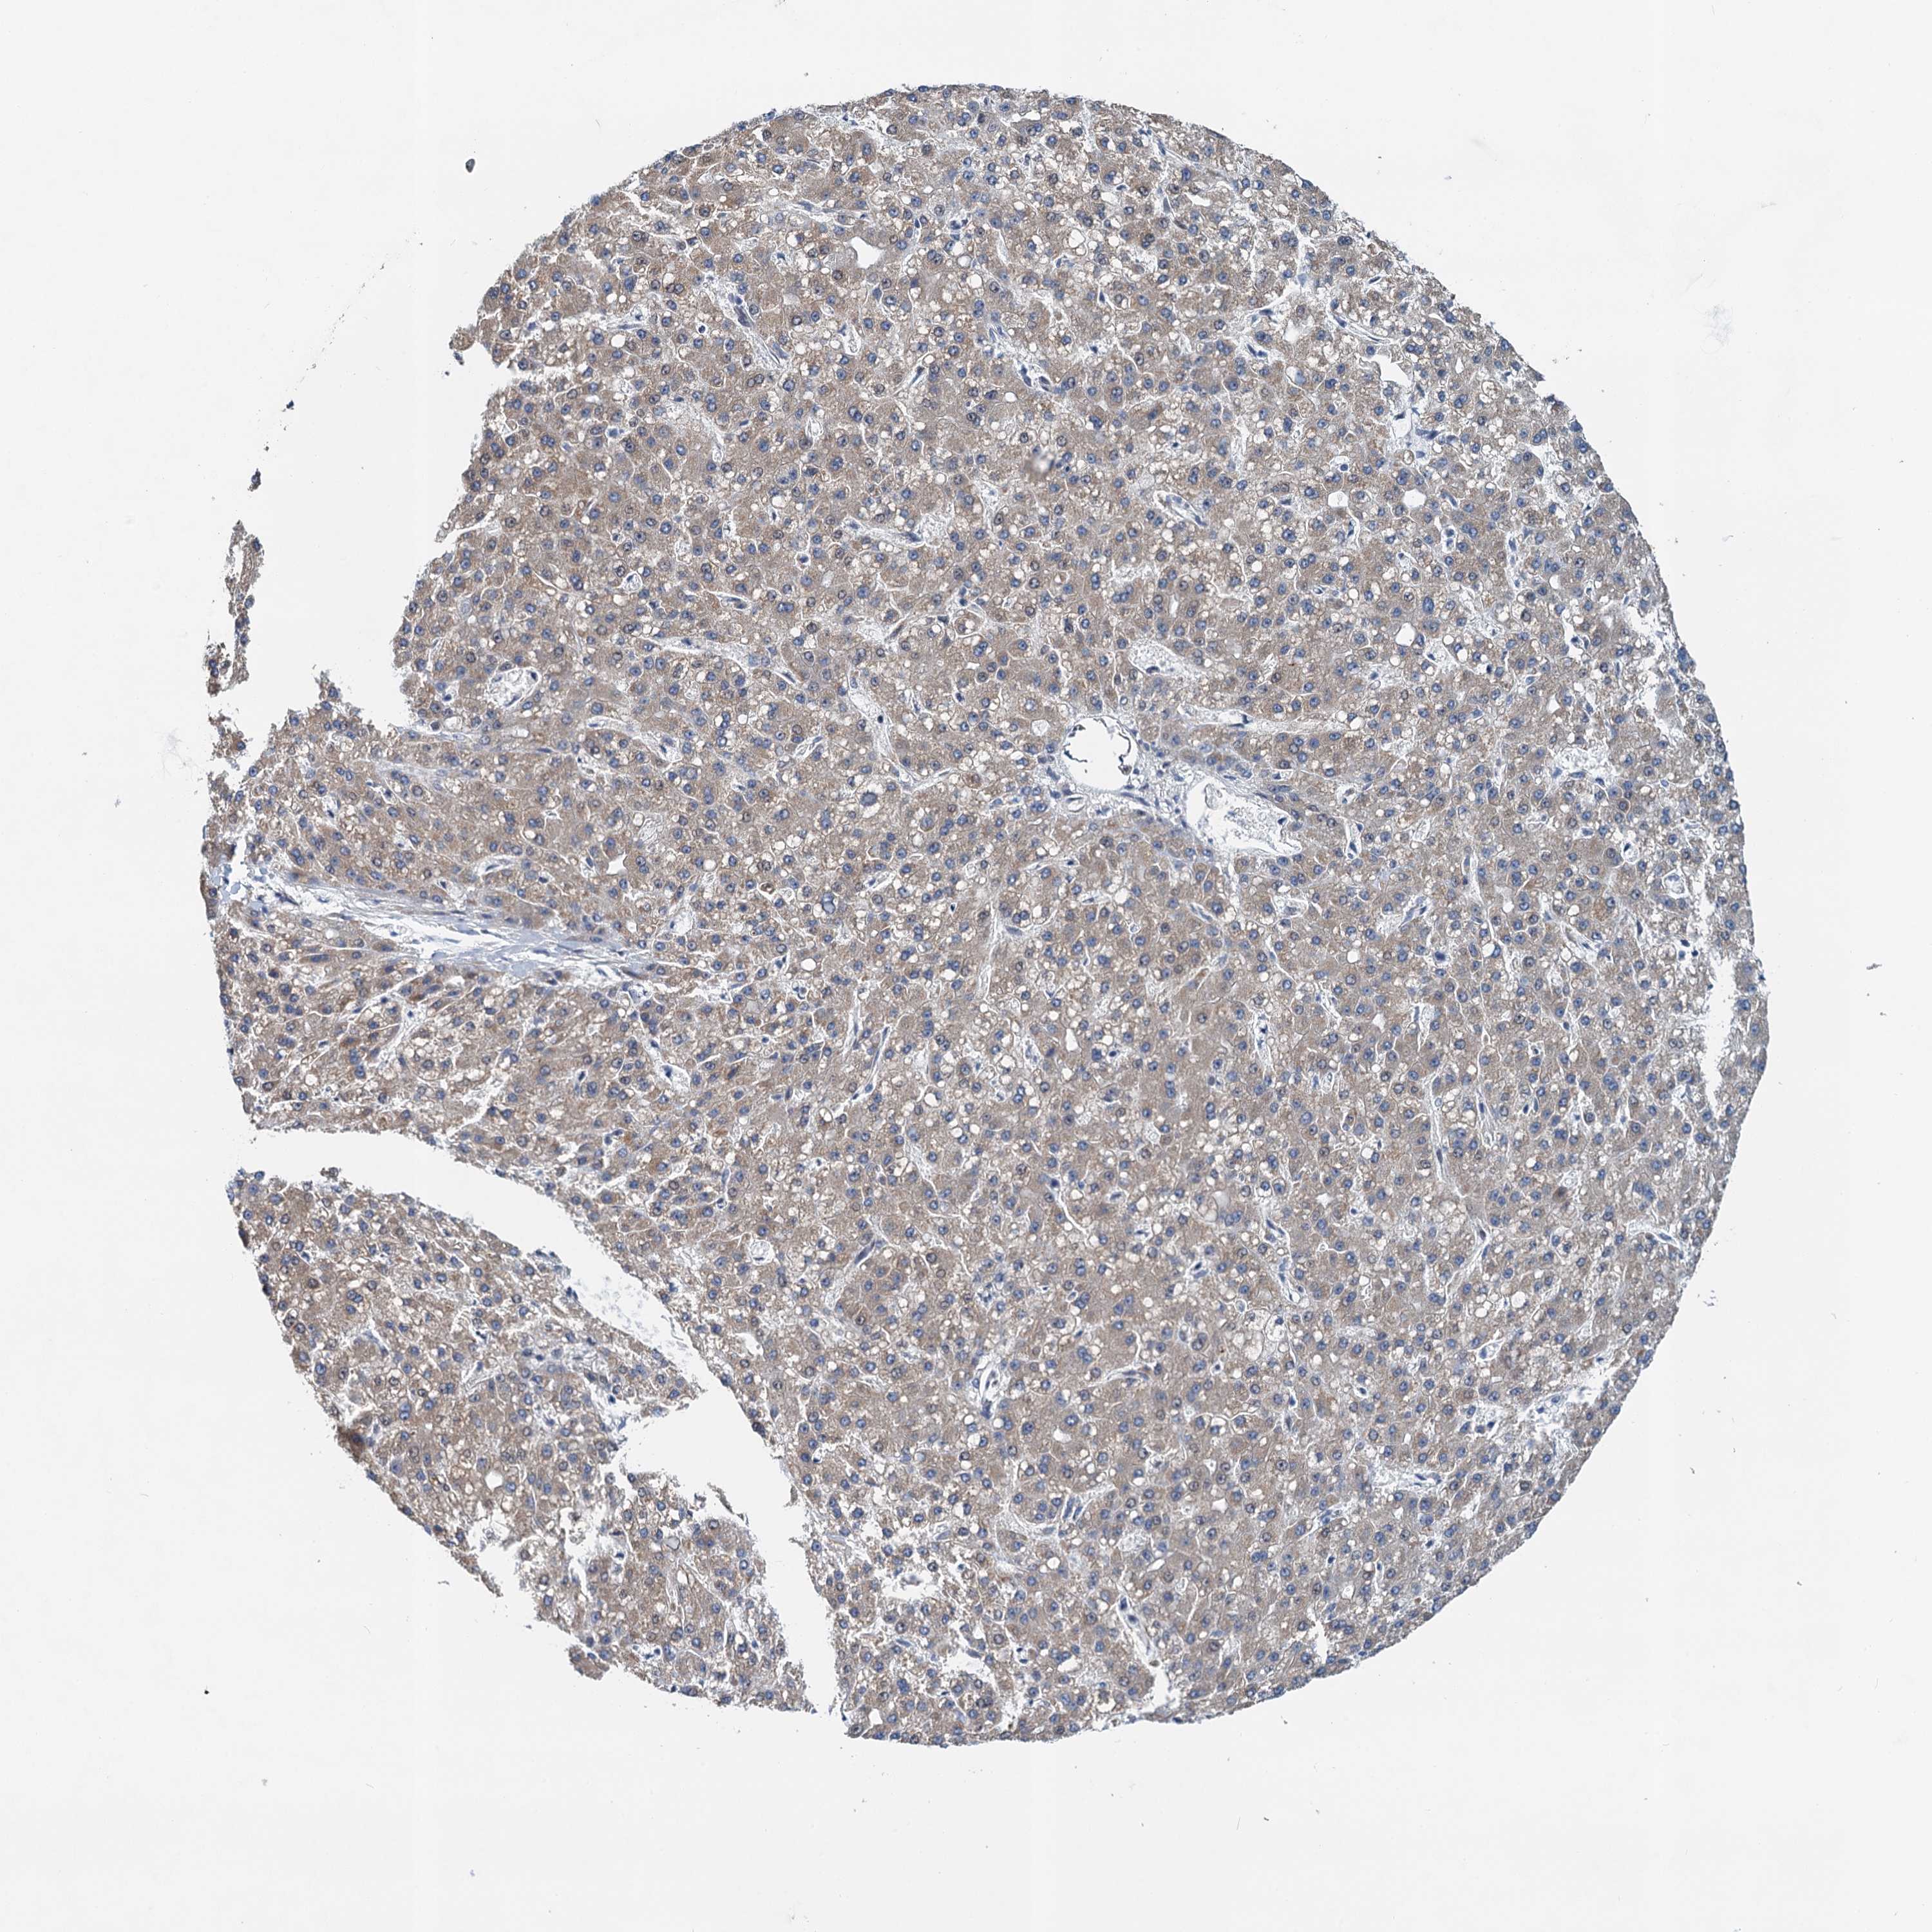

LIVER CANCER - Protein expressioni

A mouse-over function shows sample information and annotation data. Click on an image to view it in a full screen mode. Samples can be filtered based on level of antibody staining by selecting one or several of the following categories: high, medium, low and not detected. The assay and annotation is described here.

Note that samples used for immunohistochemistry by the Human Protein Atlas do not correspond to samples in the TCGA dataset.

Antibody stainingi

Antibody staining in the annotated cell types in the current human tissue is reported as not detected, low, medium, or high, based on conventional immunohistochemistry profiling in selected tissues. This score is based on the combination of the staining intensity and fraction of stained cells.

Each image is clickable and will lead to virtual microscopy that enables deeper exploration of all samples and also displays staining intensity scores, fraction scores and subcellular localization as well as patient and tissue information for each sample.

Antibody HPA039730

Antibody HPA040385

Staining

High

Medium

Low

Not detected

Intensity

Strong

Moderate

Weak

Negative

Quantity

>75%

75%-25%

<25%

None

Location

Nuclear

Cytoplasmic/membranous

Cytoplasmic/membranous,nuclear

Cholangiocarcinoma

Carcinoma, Hepatocellular, NOS